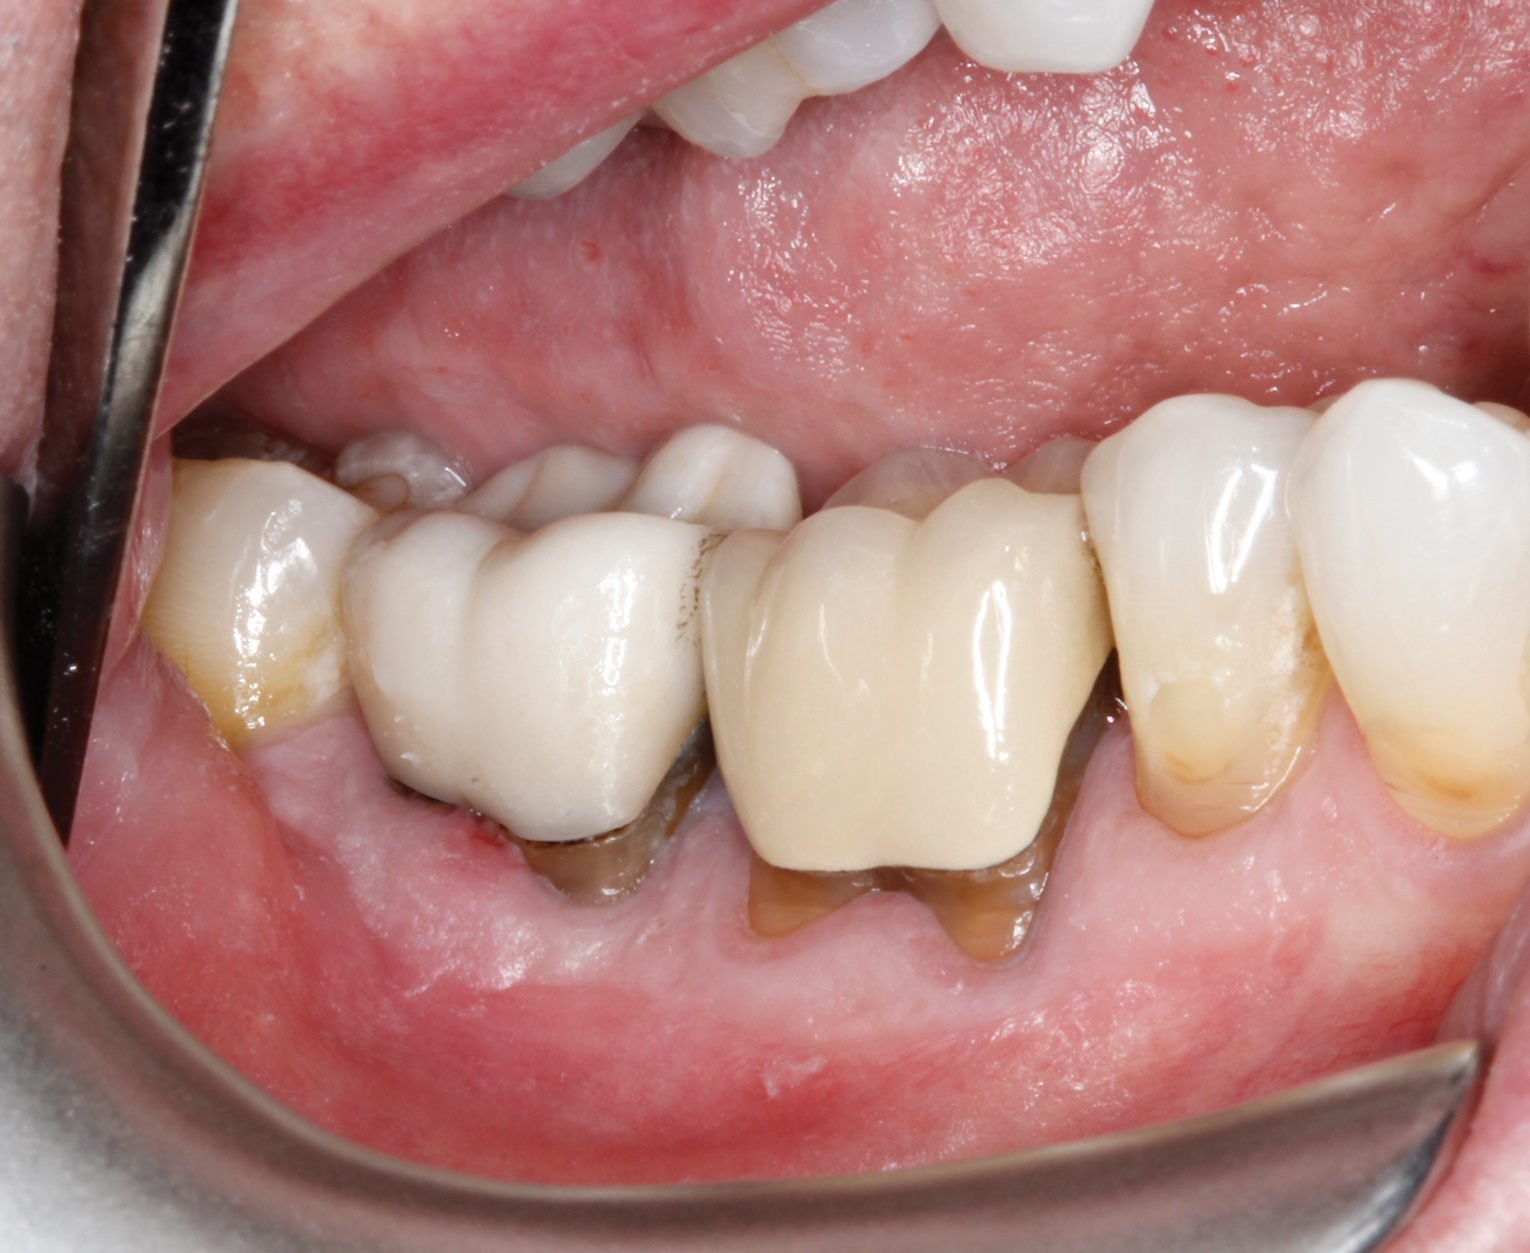

A 68-year-old male patient presented with a failing lower right second molar and retained third molar and was seeking implant restoration at the second molar site (Figure 11 and Figure 12). The patient's medical history was significant for hypertension and cardiac arrhythmia under good control.

Fig 11. Buccal view of mandibular right second molar.

Figure 11